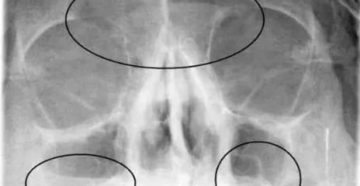

Гайморит на снимке: описание, расшифровка показателей, диагностика заболевания, методы лечения Гайморит — нагноение слизистой оболочки…